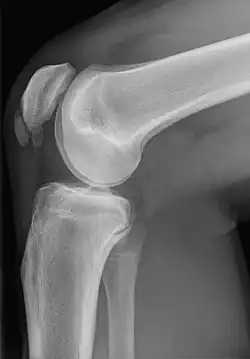

Im Röntgenbild ist eine Veränderung des Knochens zu erkennen, die Sonografie zeigt zusätzlich die Auftreibung und entzündliche Veränderung der Sehne, in der Kernspintomografie ist außerdem ein Ödem angrenzend in der Kniescheibe zu erkennen.